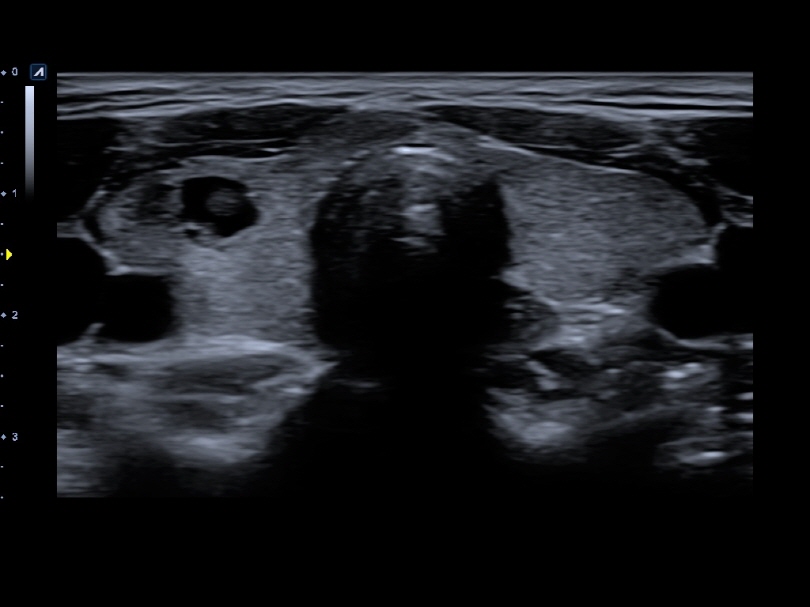

L8-17H

High density linear transducer(8-17MHz)

Application:

Breast, EM, MSK, Vascular, Small Parts

L3-12H

High density linear transducer (3-12MHz)

Application:

Breast, EM, MSK, Vascular, Small Parts

L3-12HWD

High density wide footprint linear transducer (3-12MHz)

Application:

Breast, EM, MSK, Vascular, Small Parts, Appendix

L3-12T

Linear transducer (3-12MHz)

Application:

Breast, EM, MSK, Vascular, Small Parts, Appendix